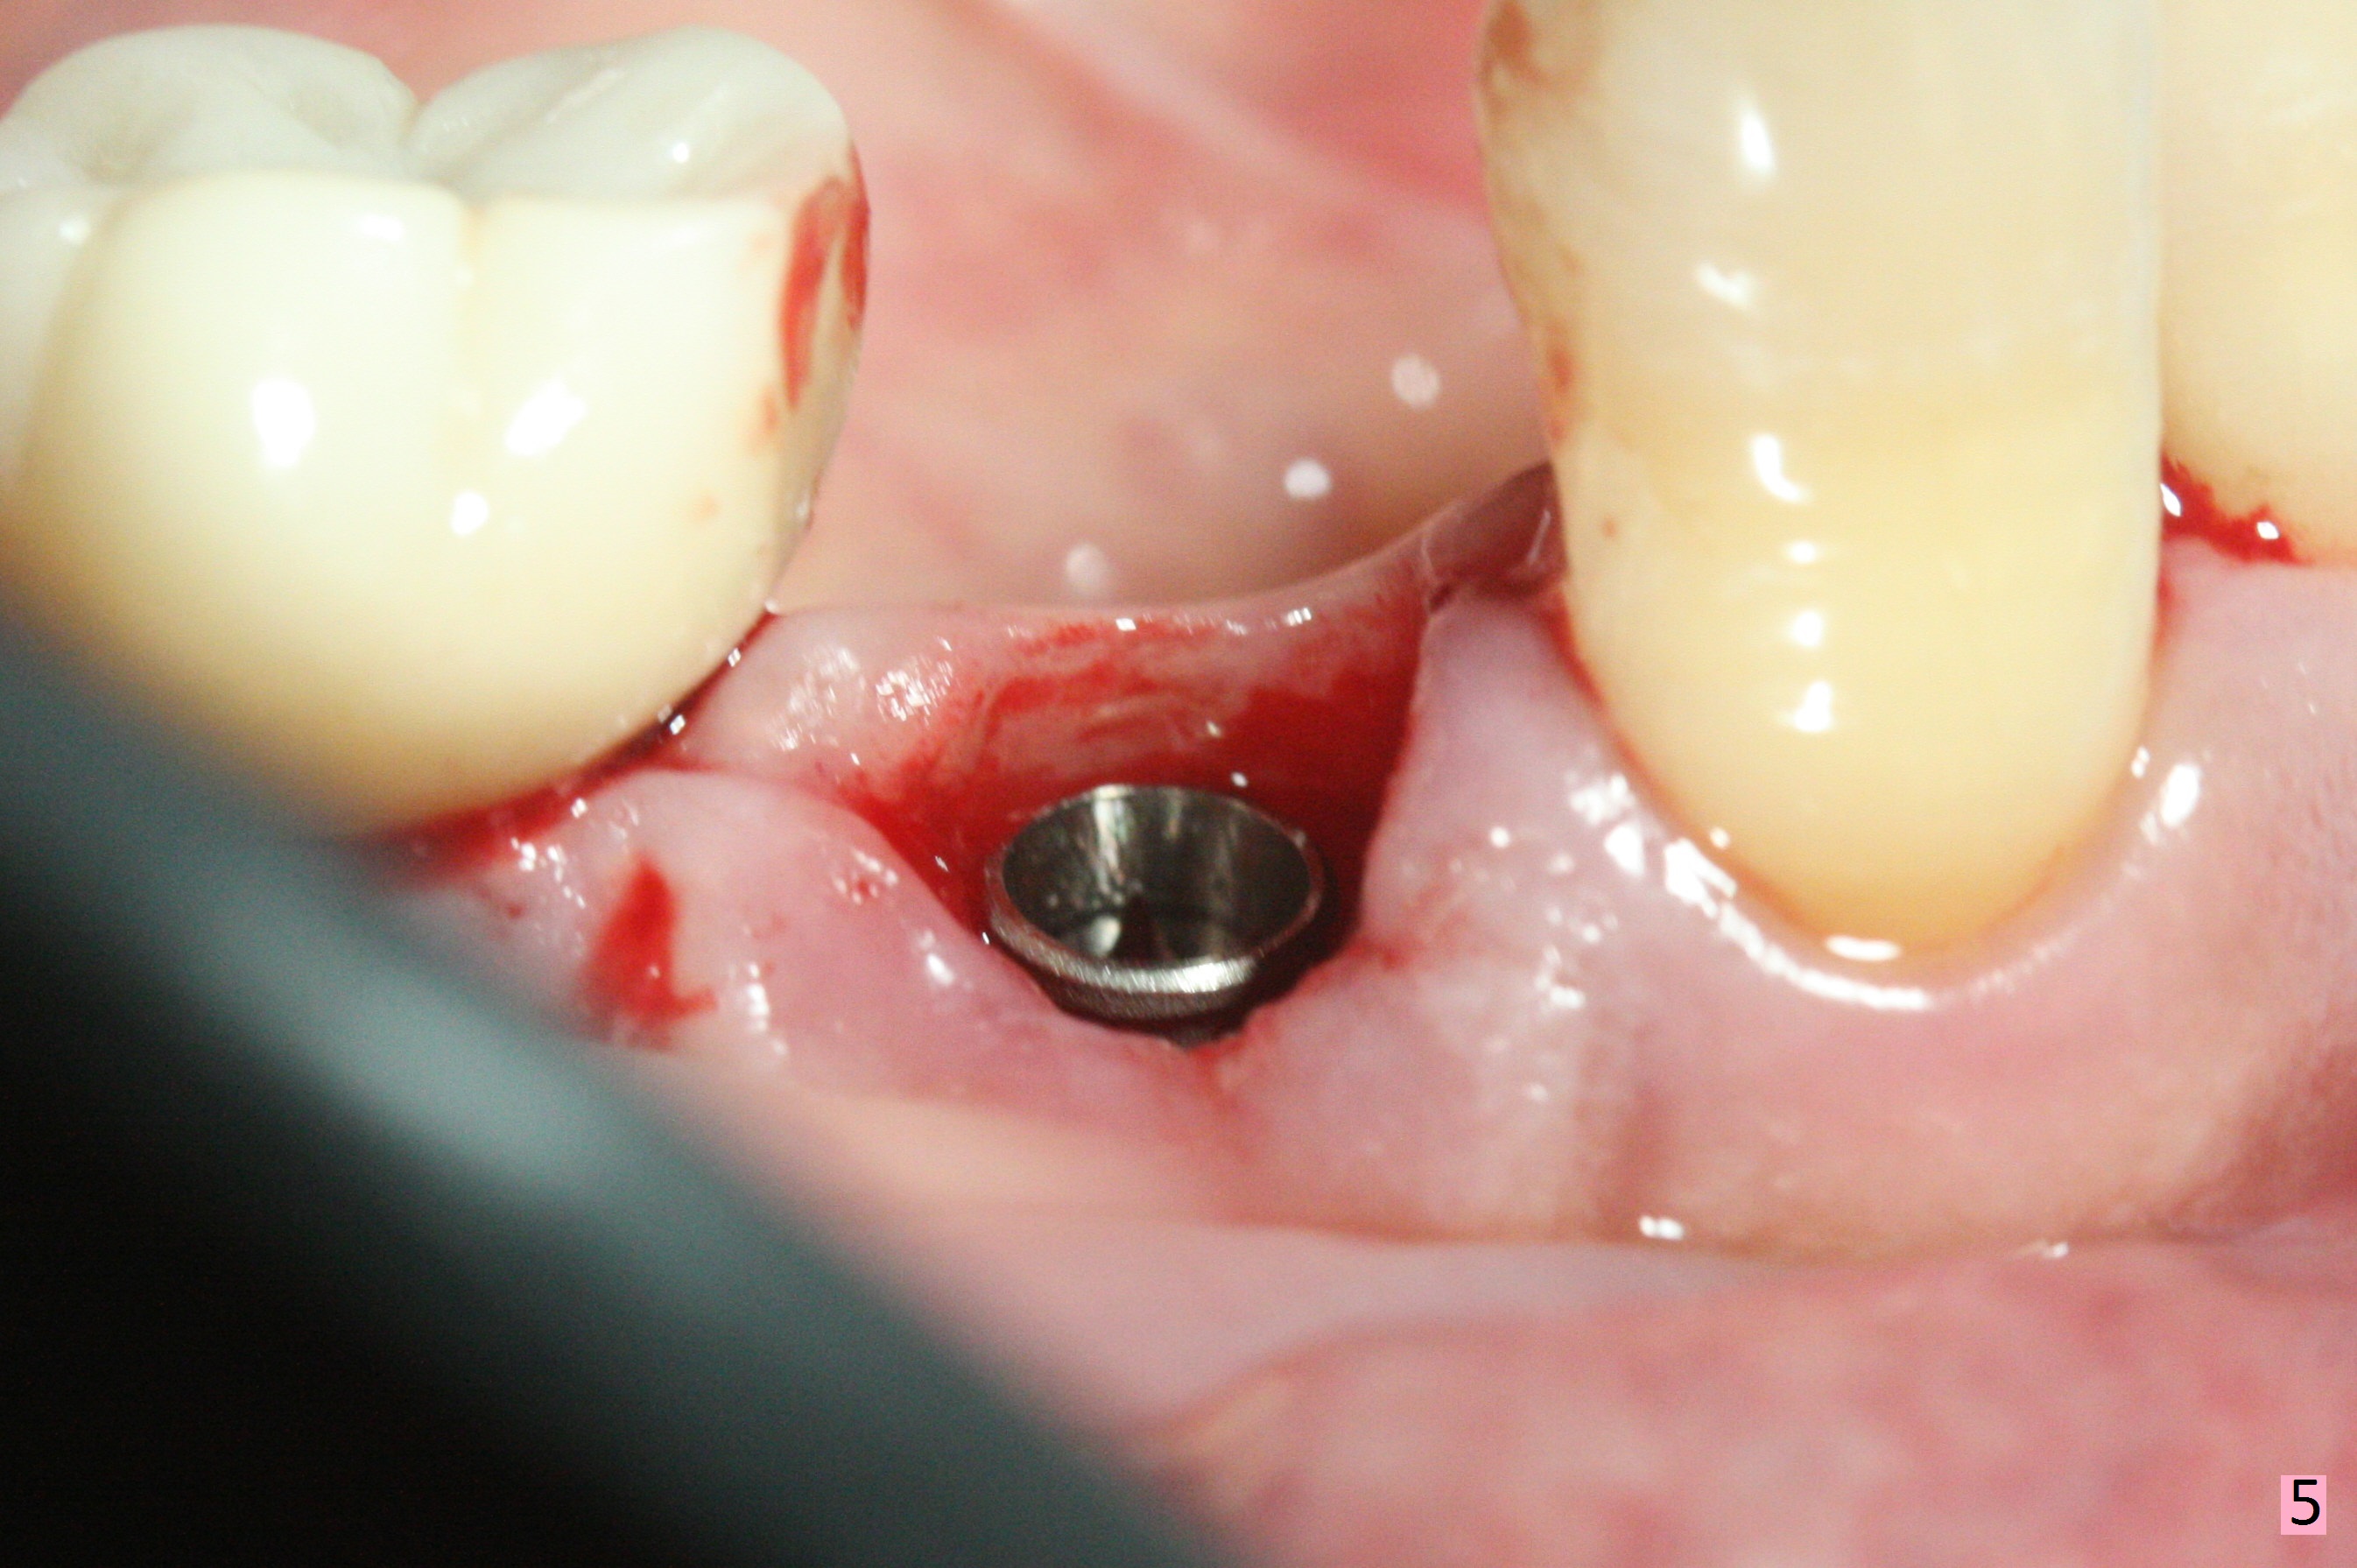

The affected tooth (#28) has buccal gingival recession (Fig.1). As expected, the buccal plate is found low after extraction. Osteotomy is established in the lingual slope of the socket with 1.5 mm drill for 13 mm (Fig.2,3). Following use of Magic Drill 3.3 mm for 13 mm, a 4x11 mm dummy implant is incompletely seated (Fig.4); it is also close to the Mental Loop (Fig.4 red line). After use of Final Drill, a 4x9 mm IBS implant is placed 4 mm and 2 mm subgingival buccal and lingual, respectively (Fig.5) with a large buccal gap (Fig.6 (40 Ncm)). After placement of allograft in the peri-implant space (Fig.7 *), a 4.5x5.7(4) mm abutment is placed (A). A piece of gauze is placed in the remaining buccal space prior to provisional fabrication (Fig.8 *). The space occupied by the gauze is later filled with collagen plug before provisional seating. The gingiva is healthy around the provisional 12 days postop (Fig.9). To reduce buccal gingival recession, the buccal margin of the provisional is shortened 4.5 months postop (Fig.10 arrow). PA taken 5.5 months postop is shown with the implant at 31. The lingual gingiva is erythematous, edematous, and recessive with +BOP and deep pockets 14 months postop (Fig.11). It appears that the small and short implant is not favorable for healing. The infected implant is removed with the missing buccal plate; bone graft is placed 15 months postop (7 months post cementation, Fig.12,13).